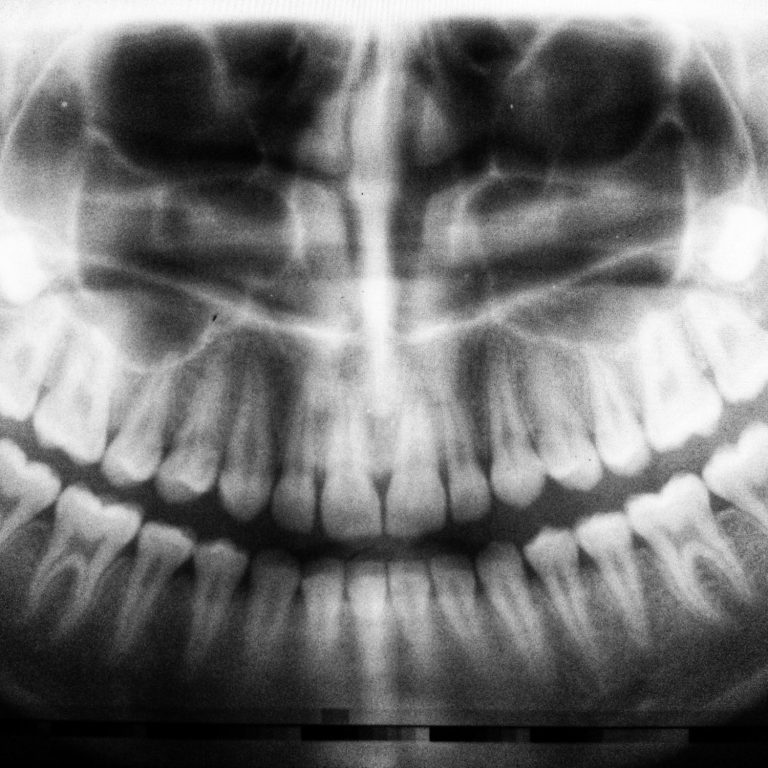

Die Parodontologie befasst sich mit der Gesundheit des Zahnhalteapparates, also des Zahnfleisches und des Kieferknochens. Eine Parodontitis, auch als Zahnfleischentzündung bekannt, ist eine der häufigsten Ursachen für Zahnverlust bei Erwachsenen. Frühzeitig erkannt, kann sie effektiv behandelt werden. In unserer Praxis setzen wir auf moderne Diagnose- und Behandlungsmethoden, um Entzündungen zu bekämpfen und Ihr Zahnfleisch langfristig gesund zu erhalten. Eine regelmäßige Vorsorge ist entscheidend, um Komplikationen vorzubeugen und Ihre Zahngesundheit zu schützen.

Die Endodontie beschäftigt sich mit dem Inneren des Zahnes, insbesondere dem Zahnmark und den Wurzelkanälen. Entzündungen oder Infektionen in diesem Bereich können starke Beschwerden verursachen und im schlimmsten Fall zum Verlust des Zahnes führen. Durch eine moderne Wurzelkanalbehandlung können wir erkranktes Gewebe entfernen, den Zahn gründlich reinigen und längerfristig erhalten. In unserer Praxis nutzen wir moderne Techniken und präzise Instrumente, um ihre Beschwerden zu lindern und ihre natürlichen Zähne nach Möglichkeit zu erhalten.